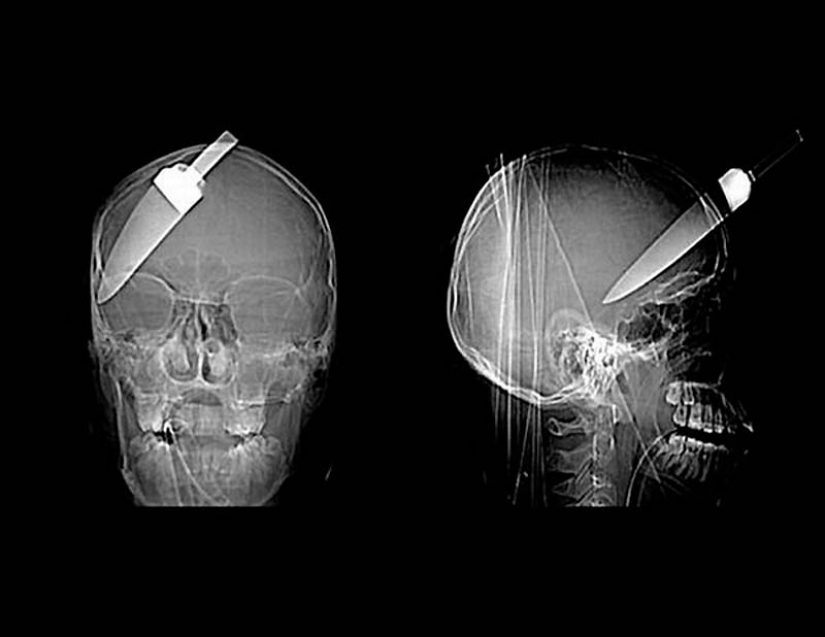

15. Knife in the head 10 year old boy. The boy survived.

18. 12-centimeter knife in the skull of a teenager.